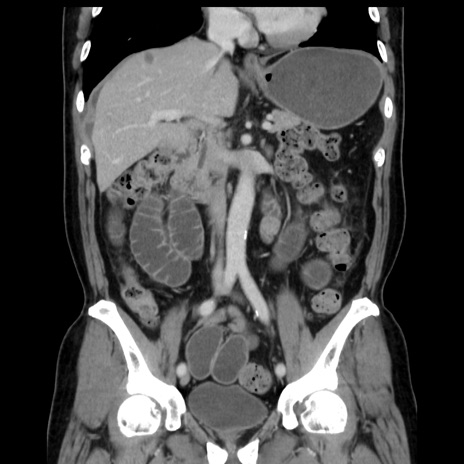

症例16(冠状断像)

【症例】 70歳代男性

【主訴】 腹痛、嘔吐

【現病歴】 約1ヶ月前より間欠的に腹痛と嘔吐あり、当院消化器内科を受診したところCTで多発する肝臓のLDAを指摘され、精査中であった。以降は消化器症状は安定していたが、2日前より嘔気と腹痛があり、同日より排便・排ガスが消失した。改善認めず、 本日、救急外来を受診した。

【既往歴】 大腸ポリープ切除後。

【身体所見】意識清明・会話良好、BT 36.3℃、BP 127/80mmHg、 P 80bpm、腹部:膨満あり、平坦・軟、上腹部正中および下腹部正中に圧痛あり、反跳痛なし、筋性防御なし。

【データ】WBC 7200、CRP 0.77